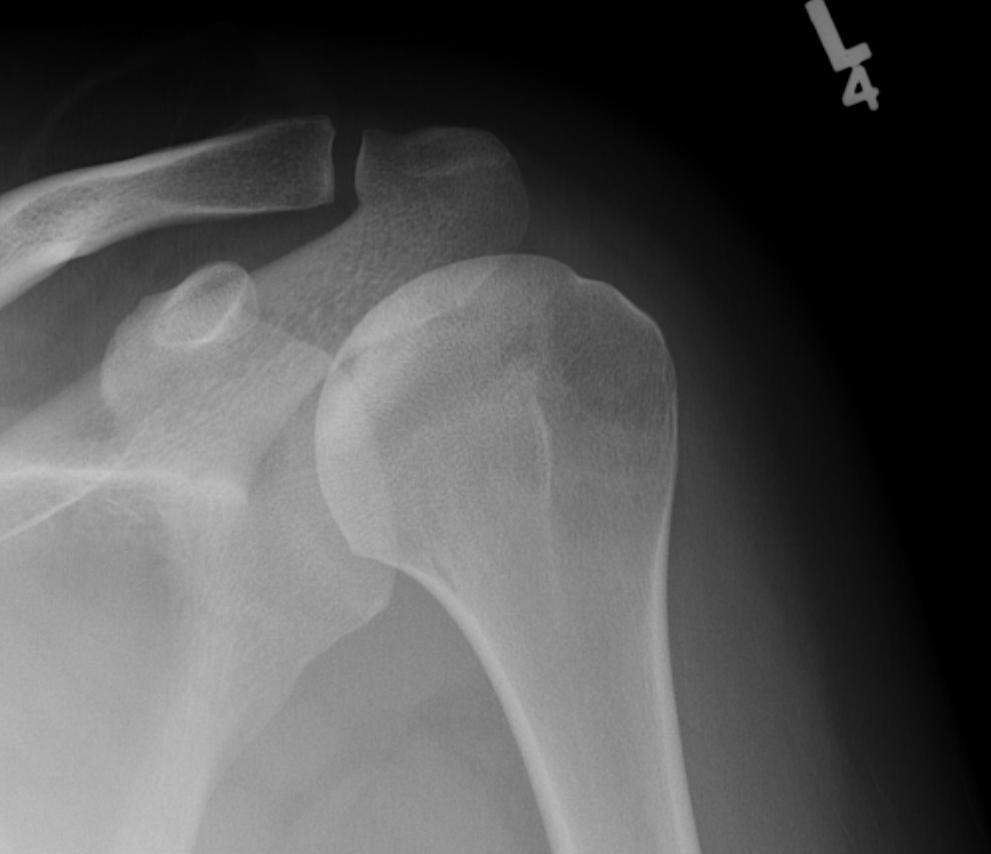

Classification / Cruess modification of Ficat-Arlet

Stage I - pre-xray change / diagnosed on MRI

Stage II - sphericity maintained / sclerotic changes in superior central head / crescent sign

Stage III - mild flattening articular surface

Stage IV - significant humeral collapse with loss integrity joint surface

Stage V - degeneration extends to involve glenoid